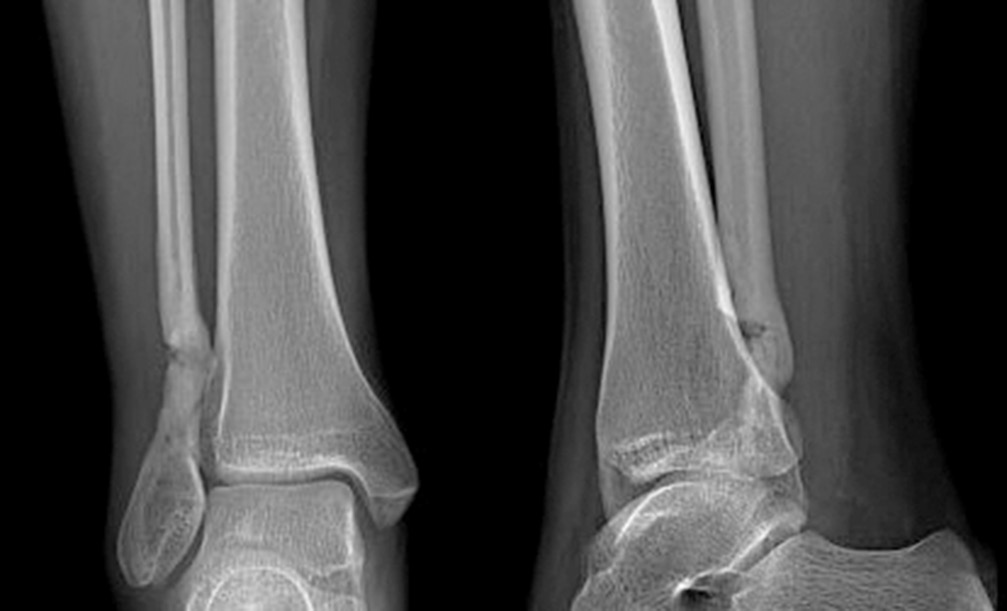

В течение 3 мес. происходила централизация болевого очага в виде усиления болевых ощущений тупого, распирающего характера в области пораженного участка кости (до 6–8 баллов по ВАШ) со значительным усилением в ночное время и при нагрузках. На рентгенограмме наблюдались облитерация костномозговой полости, на магнитно-резонансной томограмме — рубцово-спаечный процесс мягких тканей области нижней трети голени (рис. 3). Отмечались незначительное ограничение амплитуды движений в правом голеностопном суставе, небольшая отечность и температурная асимметрия (местное повышение температуры соответствующего участка кожи).

Рис. 3. Магнитно-резонансная томограмма. Рубцово-спаечный процесс мягких тканей области нижней трети правой голени

При компьютерной томографии на уровне дистального метадиафиза правой малоберцовой кости определялись деформация, остеосклеротические изменения кости на протяжении 29,0 мм с эндостально расположенными участками высокой плотности; кость локально несколько вздута, отмечались сквозные каналы после туннелизации; узурация и кистовидная перестройка задненаружной поверхности правой таранной кости, утолщение прилежащих отделов суставной капсулы правого голеностопного сустава в задненаружных отделах вследствие незначительного отека, количество синовиальной жидкости было несколько увеличено (рис. 4).

Рис. 4. Мультиспиральная компьютерная томография. Деформация, остеосклеротические изменения кости на протяжении 29,0 мм с эндостально расположенными участками высокой плотности; кость локально несколько вздута